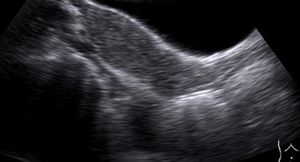

Uterine DidelphysByPratiksha Yadav, MD,Brig. Amarjit Singh, MDNovember 20th 2012Ultrasound, MRI diagnose Mullerian duct anomalies in 23-year-old female. Bleeding P/V, diffuse abdominal pain 18 days; abortion pills use after 45 days of missed period.